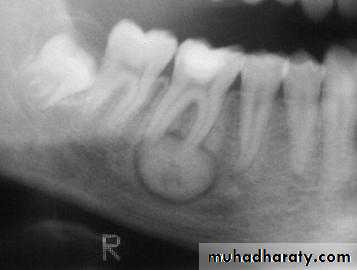

Cementoblastoma

_ True neoplasm of cementoblasts_ First mandibular molars

_ Cortex expanded without pain

_ Involved tooth ankylosed

Radiology: apical mass radiolucent halo with dense lesions

Histology: radially oriented trabeculae from

cementum, rim of osteoblasts

Treatment: complete excision and tooth

sacrifice